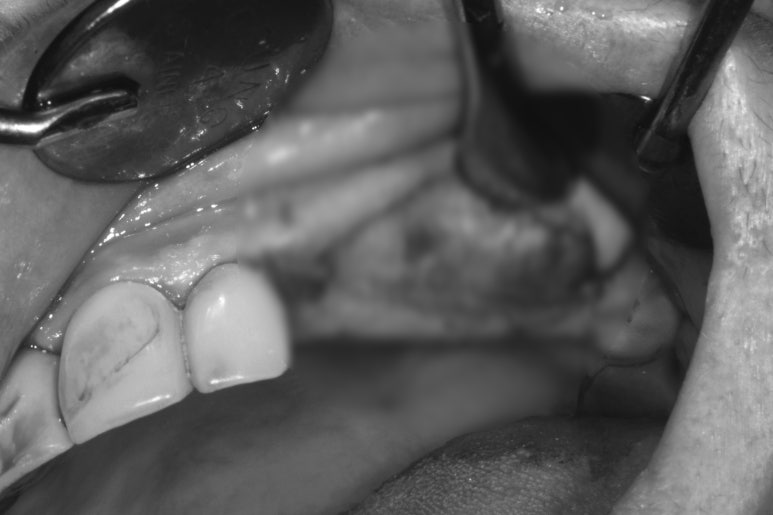

처음 오셨을 때 촬영한 정면 구강 내 사진입니다.

위 앞니 보철물은 도재 (포세린,porcelain)가 깨져있어 보기 흉한 상태였고, 대부분의 어금니가 없으신 상황..

지금까지 어떻게 식사하셨을까요 ㅠㅠ

양옆으로 보았을 때도 아래 어금니는 모두 없어진 상태이고, 쓸수 있는 치아가 많지 않았어요.